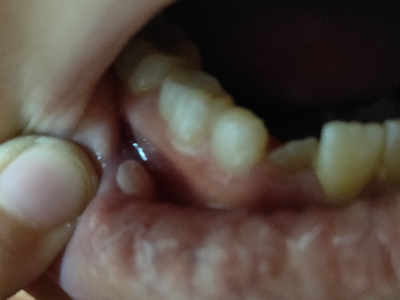

牙龈

大红疙瘩

外渗性黏液囊肿牙龈上有大红疙瘩图

外渗性黏液囊肿表现为患者下面的右侧牙龈上有一个红疙瘩,相对较大,有异物感,与周围的皮肤颜色相似,表面光滑,此病是由于局部创伤、导管系统阻塞等导致。